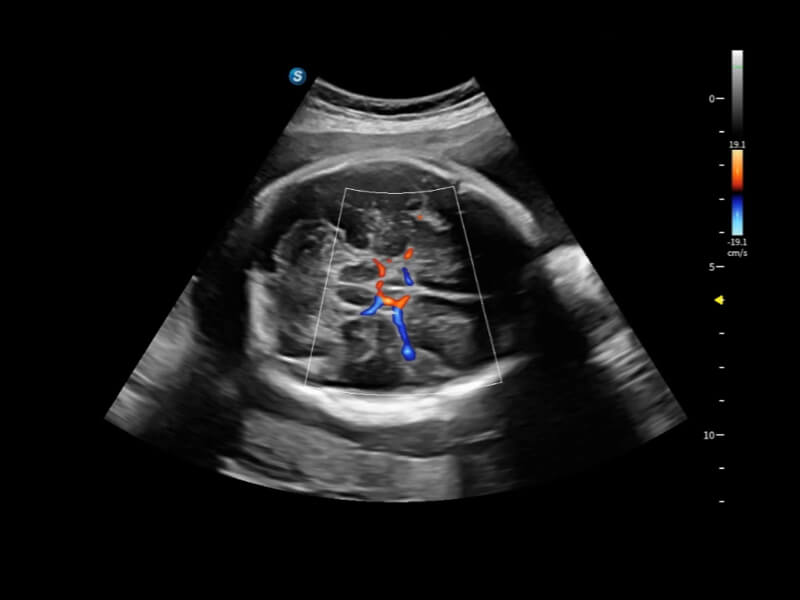

豐富的血流動(dòng)力學(xué)檢測(cè)技術(shù),可在不同醫(yī)療場(chǎng)景中高效捕捉血流信號(hào),助力臨床診療。

在傳統(tǒng)血流的基礎(chǔ)上優(yōu)化掃查和算法策略,能夠更好的抑制組織信息,提煉紅細(xì)胞運(yùn)動(dòng)信息,得到更高幀頻,高靈敏度和分辨率的血流信號(hào),還原更真實(shí)的血流動(dòng)力學(xué)。

通過(guò)光照模型,使二維血流顯示出立體的效果,增加血流的敏感性、成束性,減少外溢。可以和其他不同的血流技術(shù)聯(lián)合使用,融合不同技術(shù)的優(yōu)勢(shì)。輕松應(yīng)對(duì)微小血管,增強(qiáng)血流的立體效果,提升視覺(jué)敏感性。

通過(guò)創(chuàng)新的Matrix E自適應(yīng)濾波算法,能有效濾除軟組織和噪聲信號(hào),最大限度保留超低速微細(xì)血流的信號(hào);結(jié)合超長(zhǎng)時(shí)間域算法,極大提升細(xì)微血流的敏感性和空間分辨率,更真實(shí)的反應(yīng)組織、包塊的血流灌注情況。